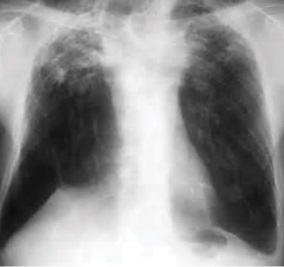

Chest x-ray of pleural thickening post-primary tuberculosis

1. Pleural thickening - Irregularity or abnormal prominence of the pleural margin, including apical capping (thickening of the pleura in the apical region). Pleural thickening can be calcified.